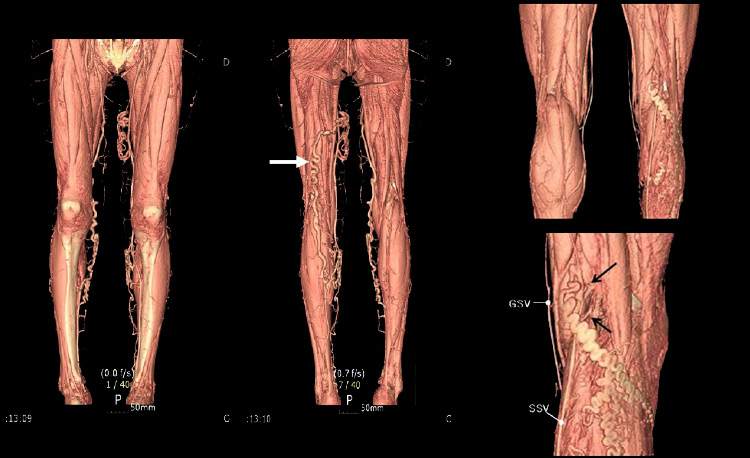

пример результатов КТ-флебографии ног, сделанной для более эффективной подготовки к операции флебэктомии

В протоколе флебографии нижних конечностей при нормальной рентгенологической картине можно увидеть такие фразы, как функция клапанного аппарата вен сохранена, проходимость вен в норме, дефектов наполнения или «обрыва» контраста не обнаружено. В случае наличия тромбоза указанные изменения присутствуют, обусловленные полной или частичной непроходимостью венозного просвета для контраста.